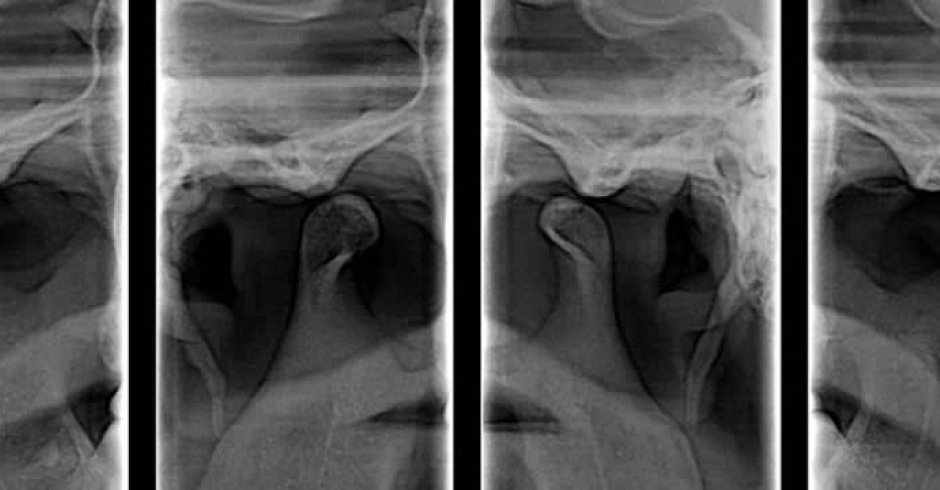

ATM

Técnica radiológica  que proporciona información sobre la Articulación Temporo –Mandibular.

Podemos observar forma de las cabezas condilares y estado de las superficies articulares desde un punto de vista lateral y la amplitud del movimiento de los cóndilos con boca abierta.